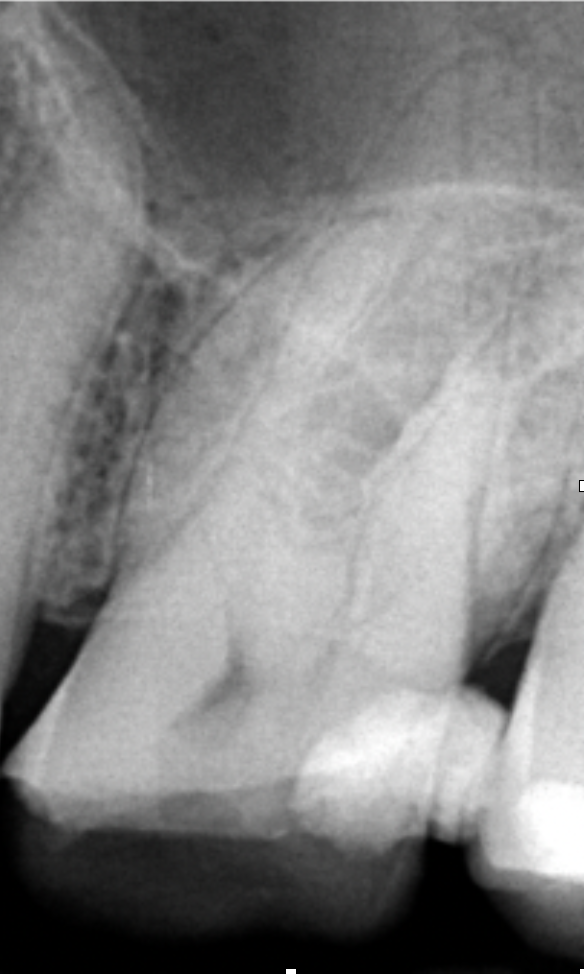

Przed leczeniem kanałowym wykonano zdjęcie rentgenowskie (ryc. 2). Ze względu na obecność żywej miazgi wykonano znieczulenie nasiękowe 1 ampułką Citocartin 100 (Molteni Dental). W osłonie koferdamu Blossom z zastosowaniem klamry 12A firmy Hygenic usunięto opatrunek. W powiększeniu mikroskopu Zumax wykonano dostęp endodontyczny wiertłem różyczkowym z węglika spiekanego o rozmiarze 014. Komora została poszerzona w kierunku mezjalno‑dystalnym. Odsłonięto ujścia czterech kanałów korzeniowych – MB1, MB2, DB1, P. Wykonano negocjację pilnikiem C‑file 10 (VDW) z pomiarem długości roboczej za pomocą endometru (VDW Reciproc Gold). Dokładna inspekcja dna komory w powiększeniu mikroskopu pozwoliła dostrzec dwa kolejne ujścia – MB3 i DB2. Występowanie kanału MB3 i DB2 jest znacznie rzadsze niż MB2 i DB1 i znajdują się one bliżej kanału podniebiennego. Negocjację kanałów MB3 i DB2 rozpoczęto od pilnika C‑file 10, zaginając narzędzie na kształt litery J (ryc. 3) – nie uzyskano pełnej długości, dlatego w kolejnym etapie użyto narzędzia 08, zaginając je na kształt litery A (ryc. 4); również nie uzyskano pełnej długości roboczej. Narzędzie C‑file 06 zagięte na kształt litery A osiągnęło otwór wierzchołkowy – potwierdzono długość roboczą i przystąpiono do wykonywania ruchów góra‑dół, bez nakręcania zegarka.

Ryc. 2. Zdjęcie rentgenowskie przed rozpoczęciem leczenia kanałowego.

Ryc. 3. Zagięcie narzędzia na kształt litery J.